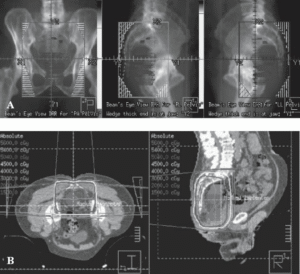

| شکل ۲۴.۱ طرح سهبعدی برای میدانهای درمانی (A) و دزیمتری (B) برای بیماری که تحت شیمیدرمانی نئوادجوانت قرار میگیرد. خطوط اطراف حجم درمان در (B) نشان دهنده سطوح دوز رسیده به حجم برنامهریزی شده و بافتهای اطراف آن هستند. |

در عمل مدرن انکولوژی تابشی، از تصویربرداری رادیوگرافی برای برنامهریزی درمانی استفاده میشود که تومورها را هدف قرار میدهد در حالی که از نظر فیزیکی تا حد امکان از بافتهای طبیعی اجتناب میکند. برنامهریزی یا دزیمتری درمان تابشی شامل ایجاد یک طرح درمان مجازی بهینه شده است. تصاویر توموگرافی کامپیوتری (CT) سهبعدی (3D) برای طراحی میدانهای تابش و محاسبات دوز استفاده میشوند و از بلوکبندی برای مسدود کردن ساختارهای بافت طبیعی استفاده میشود (شکل 24.1). یک هیستوگرام دوز-حجم (شکل 24.2) به صورت گرافیکی حجمهای درمان شده تومور و هدف منطقهای را که دوزهای مختلف دریافت میکند، نشان میدهد (شکل 24.1).